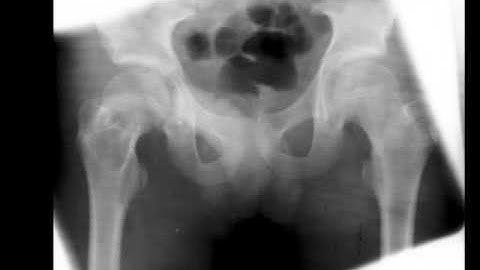

The Use of Demineralized Bone Matrix and MSC Concentration for the Treatment of the Bone Cysts